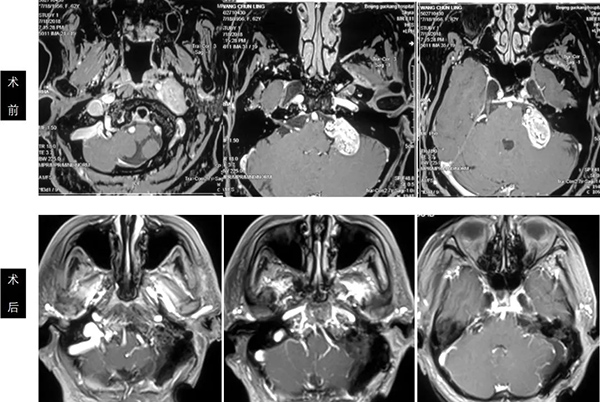

左侧颈静脉孔区神经鞘瘤手术前后

颅颈联合+经乳突经颈静脉突入路